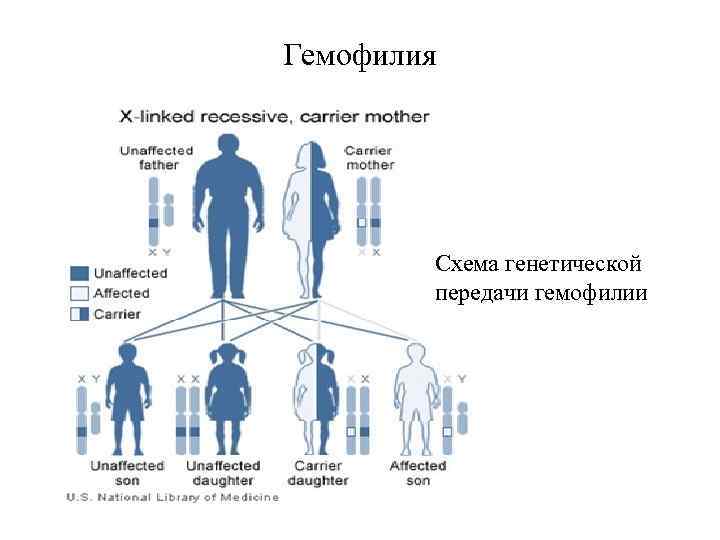

Геморрагические диатезы (2 уровень) В этом разделе мы изучаем три заболевания: 1. Аутоиммунная тромбоцитопеническая пурпура 2. Гемофилия 3. Геморрагический васкулит. В обеспечении нормального гемостаза участвуют тромбоциты (тромбоцитарный компонент), факторы свертывания крови (плазменный компонент) и сосудистая стенка (сосудистый компонент). Фибринолитическая система обеспечивает растворение избыточных тромботических масс